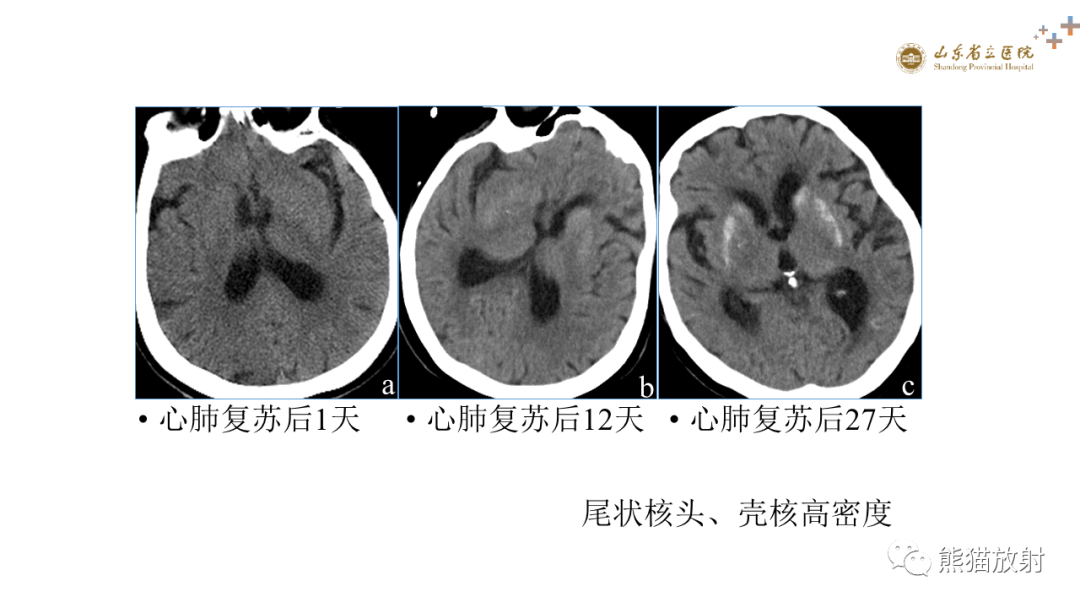

成人缺氧缺血性脑病影像学表现